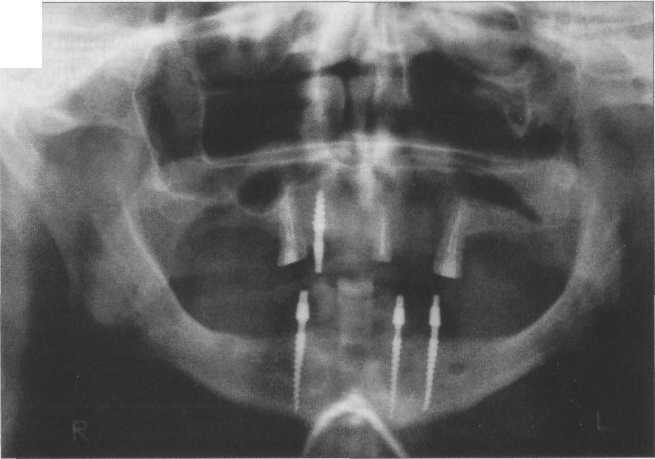

Рис. 20.20. Инволютивные изменения челюстно-лицевой области.

Адентия, атрофия нижней челюсти. Тело нижней челюсти тонкое, деформировано, угол нижней челюсти сглажен, деформация головки суставного отростка.

Инволютивные изменения обычно более выражены в нижней челюсти вследствие ее массивности и более активной механической функции. Остеопороз и атрофия, истончение костных балок губчатого вещества и наружного кортикального слоя снижают устойчивость нижней челюсти к функциональной нагрузке. В свою очередь, отсутствие зубов и атрофия альвеолярного отростка изменяют характер двигательной функции челюсти. Все эти факторы ведут к изменению формы нижней челюсти, она становится тонкой, искривленной, ее угол увеличивается, становится тупым, а головка суставного отростка деформируется и уменьшается в объеме. Трабекулярная кость приобретает крупнопетлистый рисунок, силовые линии, границы нижнечелюстного канала определяются менее отчетливо или не определяются. В области угла челюсти иногда может наблюдаться обызвествление мягких тканей, а также связочного аппарата, сухожилий и мышц у места их прикрепления к кости (рис. 20.20).

Инволютивные изменения со стороны челюстей особенно выражены при адентии, так как снижение нормальной функциональной нагрузки способствует преждевременному наступлению инволютивных изменений. Процесс старения зубов обычно заканчивается их выпадением, что приводит к усилению атрофических процессов в челюсти.